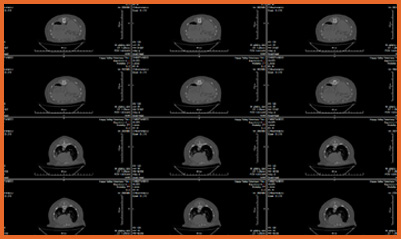

We offer general medical and surgical services with advanced diagnostic facilities. Also, we are one of the few clinics in Hong Kong that provide both CT Scan and MRI services for animals. Our team are equipped to provide detail nursing care for hospitalize pets.